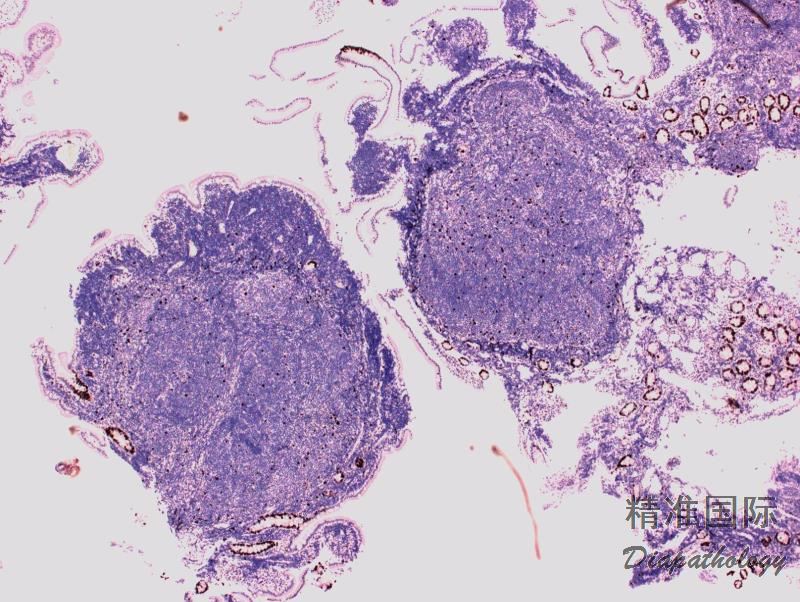

淋巴结正常结构消失,代之以紧密排例、大小和形状一致的不正常滤泡,常累及整个淋巴结或浸润到胞膜外。套区变薄、不完整、消失或极性不在。有的同时存在弥漫浸润区。偶而滤胞呈现出形状不规则或匐行性生长(类似进行性滤胞中心转化, PTGC)。

滤泡由中心细胞和不等数量的中心母细胞组成,两种细胞随机散在分布,极性和“星空”细胞消失。滤泡之间或可见浸润中心细胞。中心细胞:较中心母细胞小,核形不规则成角或有核裂,胞质少。中心母细胞:核圆形或卵圆形,呈空泡状,可见 1 ~ 3 核仁,多靠近核膜。滤泡之间或可见肿瘤细胞侵润,系中心细胞,但胞核相对规则。

免疫表型:表达 B 细胞抗原如 CD20 和 CD19,CD10+,Bcl-6+,Bcl-2+,单克隆轻链。高级别 FL,CD10 阴性相对常见。滤胞间肿瘤细胞(低级别或高级别)常弱表达或不表达 CD10,边缘区分化区域(FL 伴边缘区分化)、骨髓或外周血中的肿瘤细胞也常不表达 CD10。滤胞间区的肿瘤细胞表达 Bcl-6 也减弱。